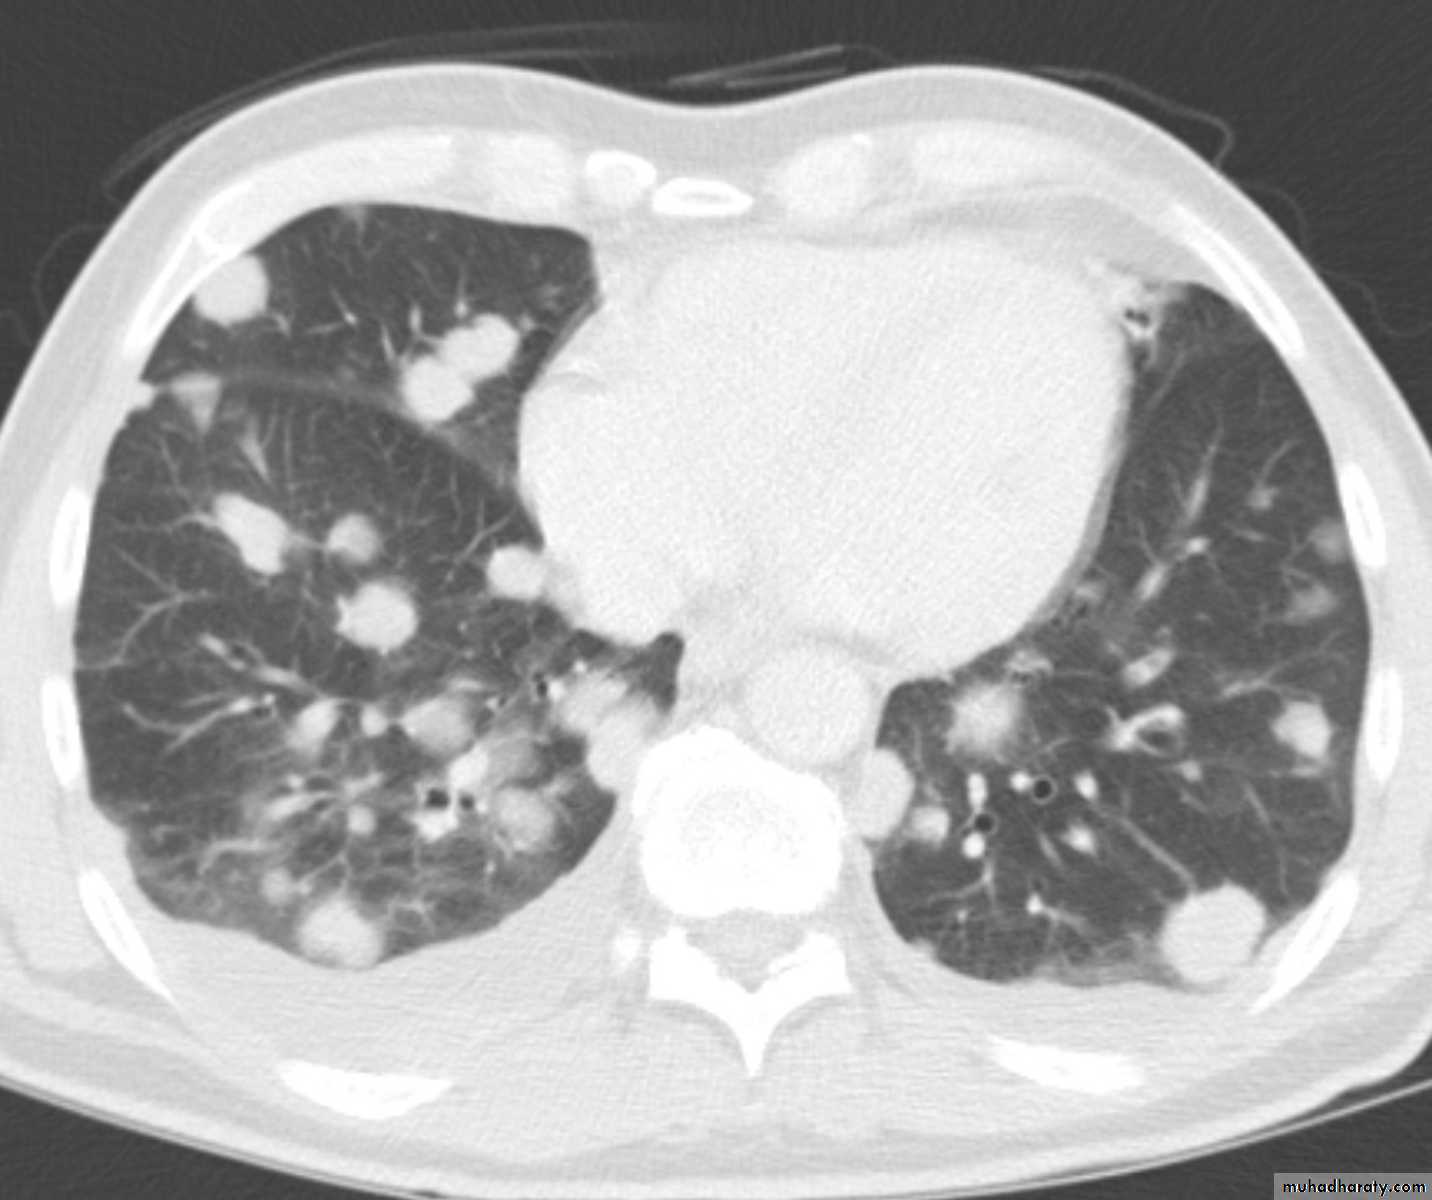

Lymphangitic carcinomatosis (LC) refers to the diffuse infiltration and obstruction of pulmonary parenchymal lymphatic channels by tumor, usually adenocarcinma from breast, lung, stomach and colon. patient usual presenting complaint is breathlessness.

Chest CT scan shows multiple round nodules and masses of varying sizes in both lungs, consistent with metastases. There are also small bilateral pleural effusions.

Computed tomography scan showing nodular thickening of interlobular septa (white arrow), seen as polygonal arcades with thickened and nodular limbs, and ground-glass opacities (black arrows).

Lymphangitic carcinomatosis